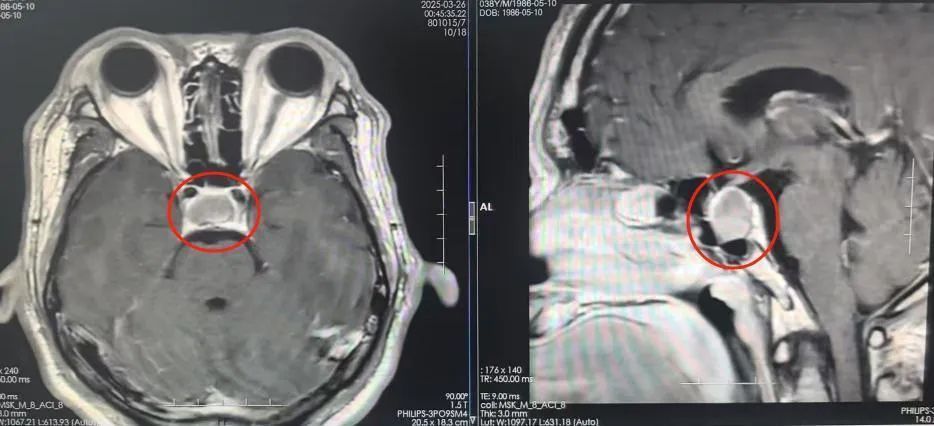

与此同时,刘杰患有高血压4年多。今年春节期间,他的血压一度飙升至190mmHg,反复头晕不适。在当地医院检查时,发现鞍区存在占位性病变。为寻求进一步治疗,4月初,刘杰来到广东三九脑科医院。

影像检查提示:鞍区占位

完善相关检查后,鲁明团队从刘杰鼻孔“打洞”,顺利切除一个大小为19mm×15mm×19mm的生长激素型垂体瘤。